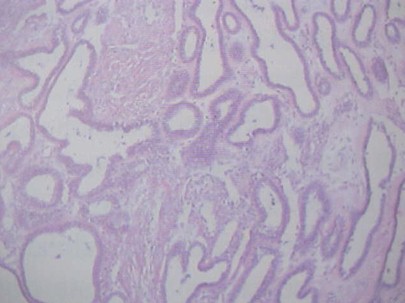

Los tumores mucinosos malignos, macroscópicamente contienen en general algunas áreas sólidas u otras con proyecciones papilares. Microscópicamente se ven papilas revestidas por células altas productoras de moco (mucinosos).

Descripción microscópica:

Los patrones glandulares tienen gran parecido con los que presentan de origen endometrial.